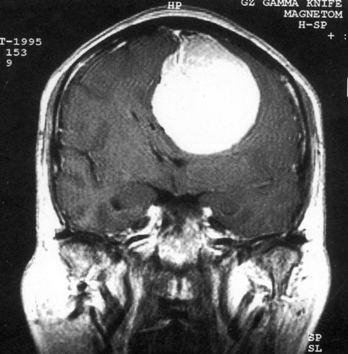

问题 病历摘要:??患者女性,37岁。大便时突起炸裂样头痛3小时,伴喷射样呕吐。既往体健。体检:T37.5℃,BP145/90mmHg,R20次/分,P85次/分。神志清楚,颅神经检查无异常,颈强直,克、布氏征(-),四肢肌力、肌张力正常,病理征(-)。 目前治疗颅内动脉瘤的主要方法有哪些?

选项 A.r刀 B.开颅动脉瘤夹闭术 C.开颅载瘤动脉夹闭及动脉瘤孤立术 D.开颅动脉瘤包裹术 E.血管内动脉瘤栓塞术 F.X刀 G.动脉瘤颈结扎术 H.颈动脉结扎术

答案 BCDE